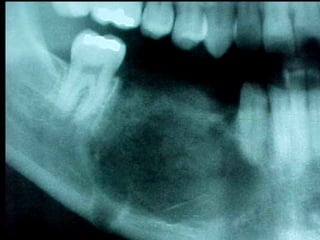

Queratoquiste odontogénico

Otro caso

Quiste mandibular